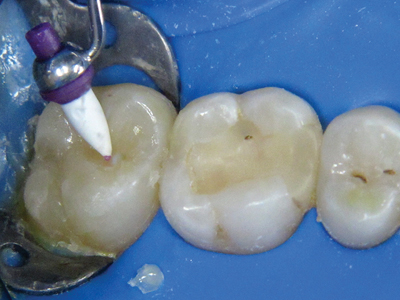

Many of our patients are attracted to the allure of cheaper dental treatment abroad. Tooth #36 in the accompanying radiograph (Fig. 1) and photo (Fig. 2) is an example of such a case. Unfortunately in this case, almost every possible iatrogenic endodontic mishap was encountered. This treatment is substandard and if done in Canada the … Read more